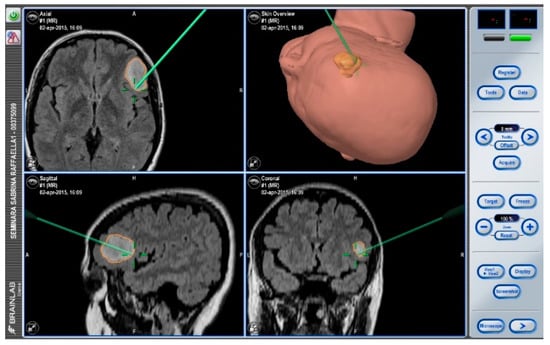

After navigation-guided identification of the tumour boundaries, an “awake” resection was performed and intraoperative identification of Broca’s area (tag 5) with “speech arrest” and inferior fronto-occipital fascicle (IFOF) with transient fonemic paraphasia was reached (tag 8) Figure 2, Figure 3 and Figure 4. Resection was then stopped.

Figure 2. Neuronavigation system adopted at our Institution.